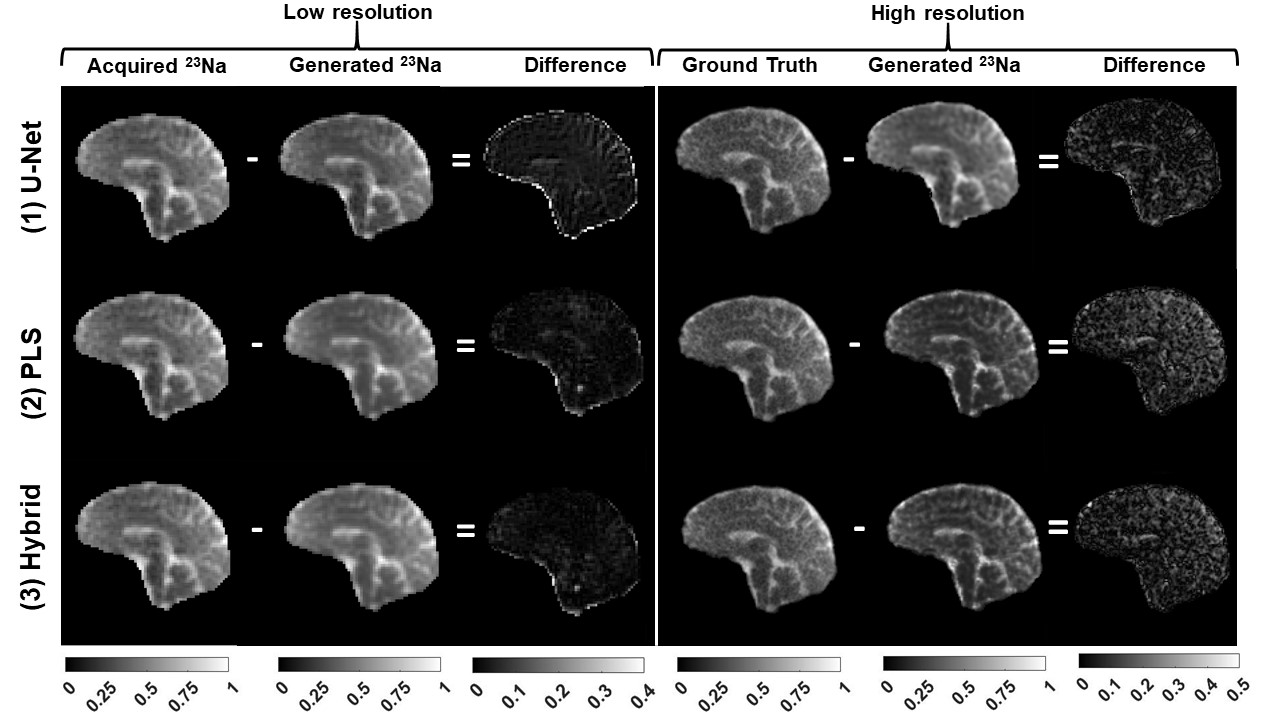

Fig. 3 shows the initial 1H and 23Na data acquired with 3D simultaneous 1H MRF/23Na MRI and the ground truth HR 23Na acquired with 3D radial GRE. Fig. 4 shows the acquired LR and ground truth 23Na images, the generated HR 23Na images, the LR 23Na generated from the 23Na HR image, and the differences between them for both LR and HR. Table 1 shows the statistical parameters calculated for each method.

The three methods showed M-SSIM>0.95 between the generated HR image and the HR ground truth. The hybrid method showed better performance than the PLS method with fewer iterations. The hybrid method showed the highest similarity between generated and acquired LR images (i.e. the highest fidelity), while the U-Net method showed the highest similarity between the generated and the ground truth HR images. However, the generated HR image from U-net looks blurrier than the images generated from the other methods.

Figure 4: Results: comparison between acquired and generated 23Na images from each method. On the right side are shown the absolute value of the difference between LR and HR images, respectively.